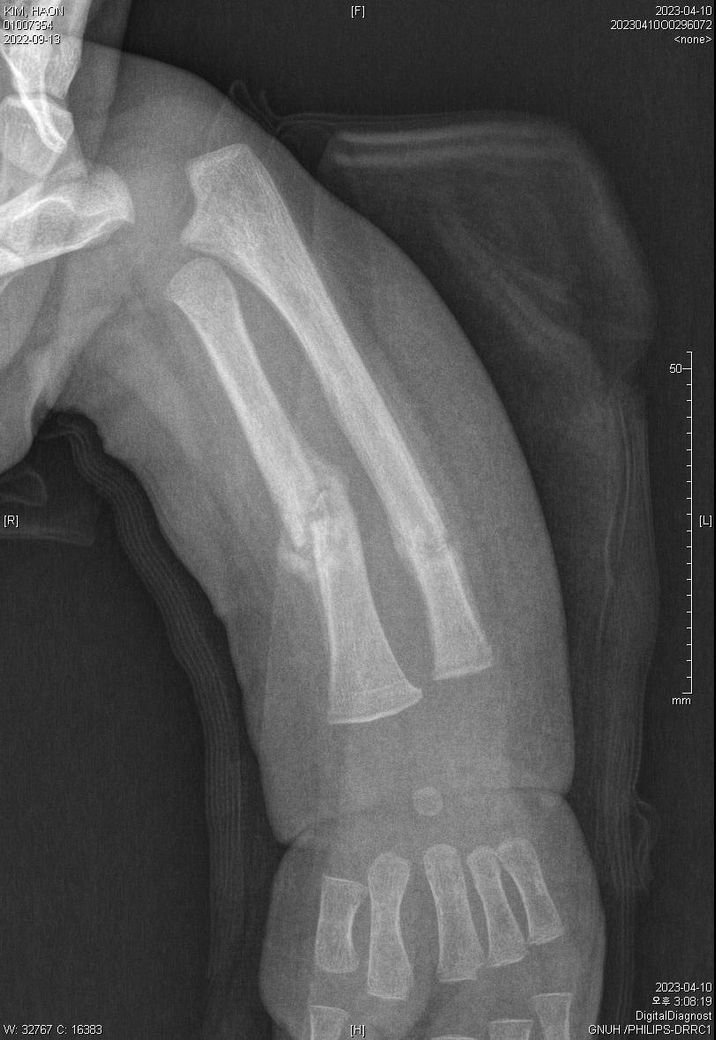

다름이 아니라, 첨부드린 엑스레이(X-ray) 사진처럼 골절 사실을 알게 되고 골절 발생 시점 대략적으로나마 추정시기를 파악하려고 문의 드리게 되었습니다

1) 3월 30일 촬영한 X-ray만으로 정확한 골절 시기를 100% 특정하는 데에는 한계가 있다는 점 충분히 인지하고 있기에 촬영날짜 기준으로 대략적으로 어느정도 시점에서 발생되었을 것으로 추측(ex 당일, 7~10일전, 7~14일 전, 10일 ~ 20일전, 14일 ~ 30일전 등등등)되는지 이해하고 싶습니다.

첨부드린 파일에도 있지만 4월 10일 사진에서는 유합 직전의 상당량의 켈로스 라는 것이 발견된다고 합니다.

• 1번 째 사진

다만 "3월 30일 영상에서 골절선이 비교적 뚜렷하고, 4월 10일에 상당한 가골(callus)이 형성"된 점을 종합하면 "골절은 3/30 당일보다는 최소 수일~2주 이상 이전에 발생했을 가능성이 높습니다."

영아(12개월)는 성인보다 "가골 형성이 빠르기 때문에, 4/10의 소견은 대략 골절 후 10~21일 전후 범위"로 해석하는 것이 의학적으로 가장 보수적 입니다.

즉, 의학적 추정 범위로는 "3월 중순 전후(약 1~3주 전 발생)"가 합리적 이며, 그 이상 정밀한 특정은 영상만으로는 어렵습니다.

올려주신 사진을 참고하였을 때 3월말에는 켈로스(가골)형성이, 4월에는 유합이 진행되고 있는 상태를 고려해볼 수 있겠습니다.

회복 경과를 바탕으로 대략적인 시점을 고려하여 보자면 3월 말 시점에서 약15-20일 정도의 기간을 골절 발생시기로 의심해볼 수 있겠지만, 정확한 소견은 관련 전문의의 의견을 들어보심이 좋습니다.